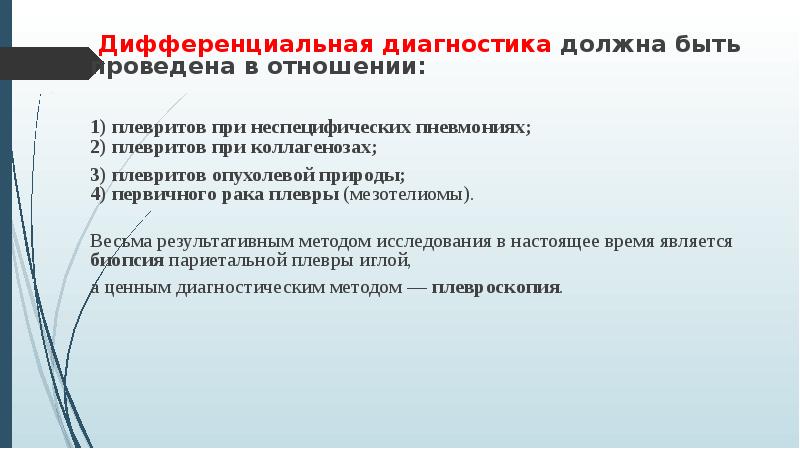

Дифференциальная диагностика заболеваний плевры